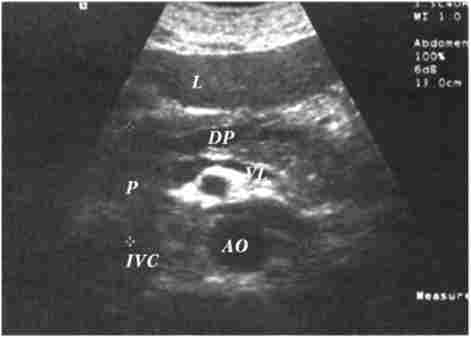

Ультразвукове дослідження (рис. 20.6) - одне з найбільш інформативних і притому неінвазивних методів дослідження ПЖ - має здійснюватися у всіх випадках, коли підозрюється її патологія.

Ультразвукове дослідження при хронічному панкреатиті

Мал. 20.6. Ультразвукове дослідження при хронічному панкреатиті:

DP - розширений проток підшлункової залози; L - печінку; Р - підшлункова залоза; VL - селезеночная вена; IVС - нижня порожниста вена; АТ - аорта

У нормі ПЖ має рівні, чіткі контури і гомогенну структуру, а діаметр головного панкреатичного протоку не перевищує 1,5-2 мм. При патології може виявлятися загальне збільшення розмірів органу з рівномірним зменшенням ехоплотності, що свідчить про набряк. Зменшення розмірів залози, неоднорідність структури, наявність дрібних ділянок ущільнення тканини, а також нечіткість контурів можуть говорити про фіброзних змінах в залозі, а невеликі різко виражені ехоположітельние вузлики - про очаговом звапнінні паренхіми.

Ехоструктури високої щільності, розташовані в протоці і дають феномен «ультразвукової доріжки», служать ознакою внутрішньопротокових конкрементів.

Рідинні освіти (помилкові кісти, уповільнені абсцеси) представляються на ехограмі округлими ділянками значно зниженою ехоплотності з більш-менш чіткими контурами і спинним посиленням. Добре сформовані хибні кісти з рідким вмістом мають округлу або овальну форму, гомогенні і оточені чітко вираженою капсулою. Вміст несфор- мировалось кіст і абсцесів може бути неоднорідним через наявність в них крім рідини тканинних секвестрів і детриту.